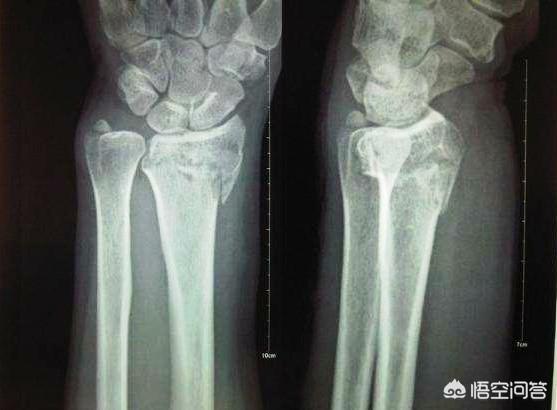

骨折后拍CT,还是DR平片是要看骨折的具体情况的,如果是容易恢复的部位,并且骨折情况比较单一的,通过手法复位就可以了,一般拍平片就可以,下图就是一个典型的克雷士骨折,也就是桡骨远端骨折的平片:

一般情况下,如果是单纯的某个四肢关节的外伤,优先选择DR平片检查,一些常见的骨折,比如说桡骨远端骨折,可以通过手法复位以后,使断端对位良好,然后再行石膏或夹板外固定的就可以的,单纯拍个平片就可以进行诊断治疗了。并且价格也在可以在受范围内,单部位平片正侧位的价格在110元左右。